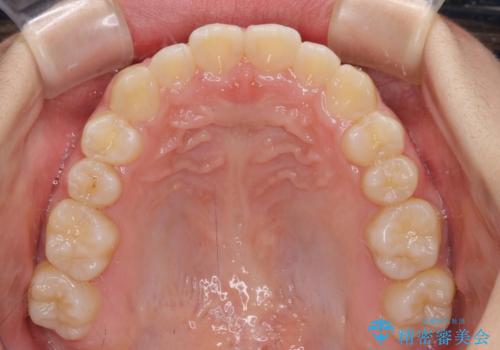

上下の骨幅を改善したことで、スムーズに歯列矯正を行うことができました。

インビザライン治療開始直後に遠方に引っ越しをされたため、通院間隔が長くなり、治療期間が長くなりましたが、しっかりと治療を行うことができました。